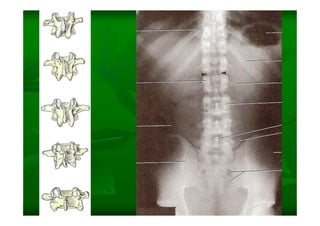

Este documento describe la columna vertebral humana. Está compuesta de 33 vértebras divididas en 7 cervicales, 12 torácicas, 5 lumbares, 5 sacras y 4 cóccigeas. Cada vértebra posee un cuerpo, pedículo, apófisis transversas, apófisis espinosa e inferior y laminas. Las curvaturas de la columna son la lordosis cervical y lumbar y la cifosis torácica y sacra.